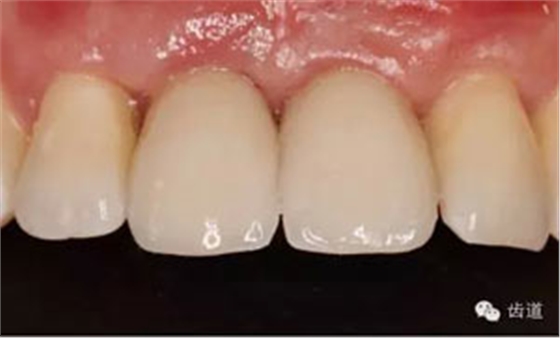

基臺(tái)就位

牙冠就位

骨環(huán)技術(shù)可以解決水平和垂直向的骨不足,但一般采用自體骨。自體骨雖然是骨移植的金標(biāo)準(zhǔn),但是需要在第二術(shù)區(qū)取骨,患者疼苦較大。同種異體骨塊來(lái)自于人類,和自體骨的結(jié)構(gòu)非常類似,成骨性能良好。故筆者選用同種異體骨塊進(jìn)行骨環(huán)手術(shù),在國(guó)內(nèi)外都是首次。該病例筆者隨訪觀察了一年,目前骨環(huán)比較穩(wěn)定。 白石 男 重慶醫(yī)科大學(xué)附屬口腔醫(yī)院種植科主治醫(yī)師,講師,碩士; 國(guó)際種植協(xié)會(huì)高級(jí)??漆t(yī)師,華西口腔醫(yī)學(xué)院碩士畢業(yè)生; 從事種植外科和種植修復(fù)臨床工作10年; 曾接受系統(tǒng)化種植培訓(xùn),有豐富口腔種植治療經(jīng)驗(yàn),擅長(zhǎng)復(fù)雜種植的設(shè)計(jì)與修復(fù),對(duì)全口種植義齒、種植美學(xué)修復(fù)技術(shù)和常規(guī)精密義齒修復(fù)有較深研究。 參加國(guó)內(nèi)外多次會(huì)議,并屢次獲得病例比賽獎(jiǎng)勵(lì)。